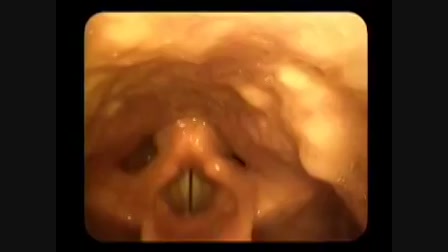

Apa és Micus

Category: fun

Meg kell nézni.